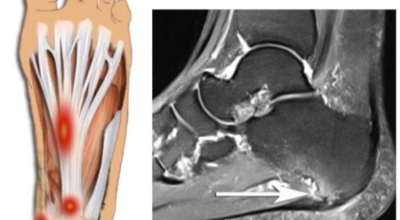

족저 근막이란 발가락 시작지점부터 발뒤꿈치뼈까지 발바닥 전체를 감싸고 있는 두꺼운 막을 말합니다. 족저 근막은 발바닥 아치를 지속시켜 발바닥이 지면을 내딛음으로써 발생하는 충격을 흡수하는 중요한 역할을 수행하고 있답니다. 이 족저 근막에 일차적으로 서서히 조직 손상이 일어나고 계속적인 활동으로 말미암아 염증이 커지면서 발 뒤꿈치 부근 통증을 일으키게 되는데 염증은 무리하고 반복적인 동작, 많은 사용으로 마찰에 의해 발생합니다.

족저 근막염은 염증에 의한 손상 및 통증을 유발하는 질환인데요 족저 근막염 증상은 일반적인 발뒤꿈치 통증 하글런드 병변의 기형으로 알려져 있으고 아킬레스 건과 관련이 깊다고 합니다. 특히 근육이 덜 풀린 아침 시간 대는 보행 시 날카롭고 바늘로 찌르는 듯한 심한 통증을 느끼게 된다고 합니다. 하지만 아침 시간 대를 지나 오후에 접어들면서 어느 정도 통증은 서서히 감소하기 시작한다고 하는데요 초기 증상이 나타난다면 꼭 전문의를 찾아 조기치료하는 것이 바람직합니다.